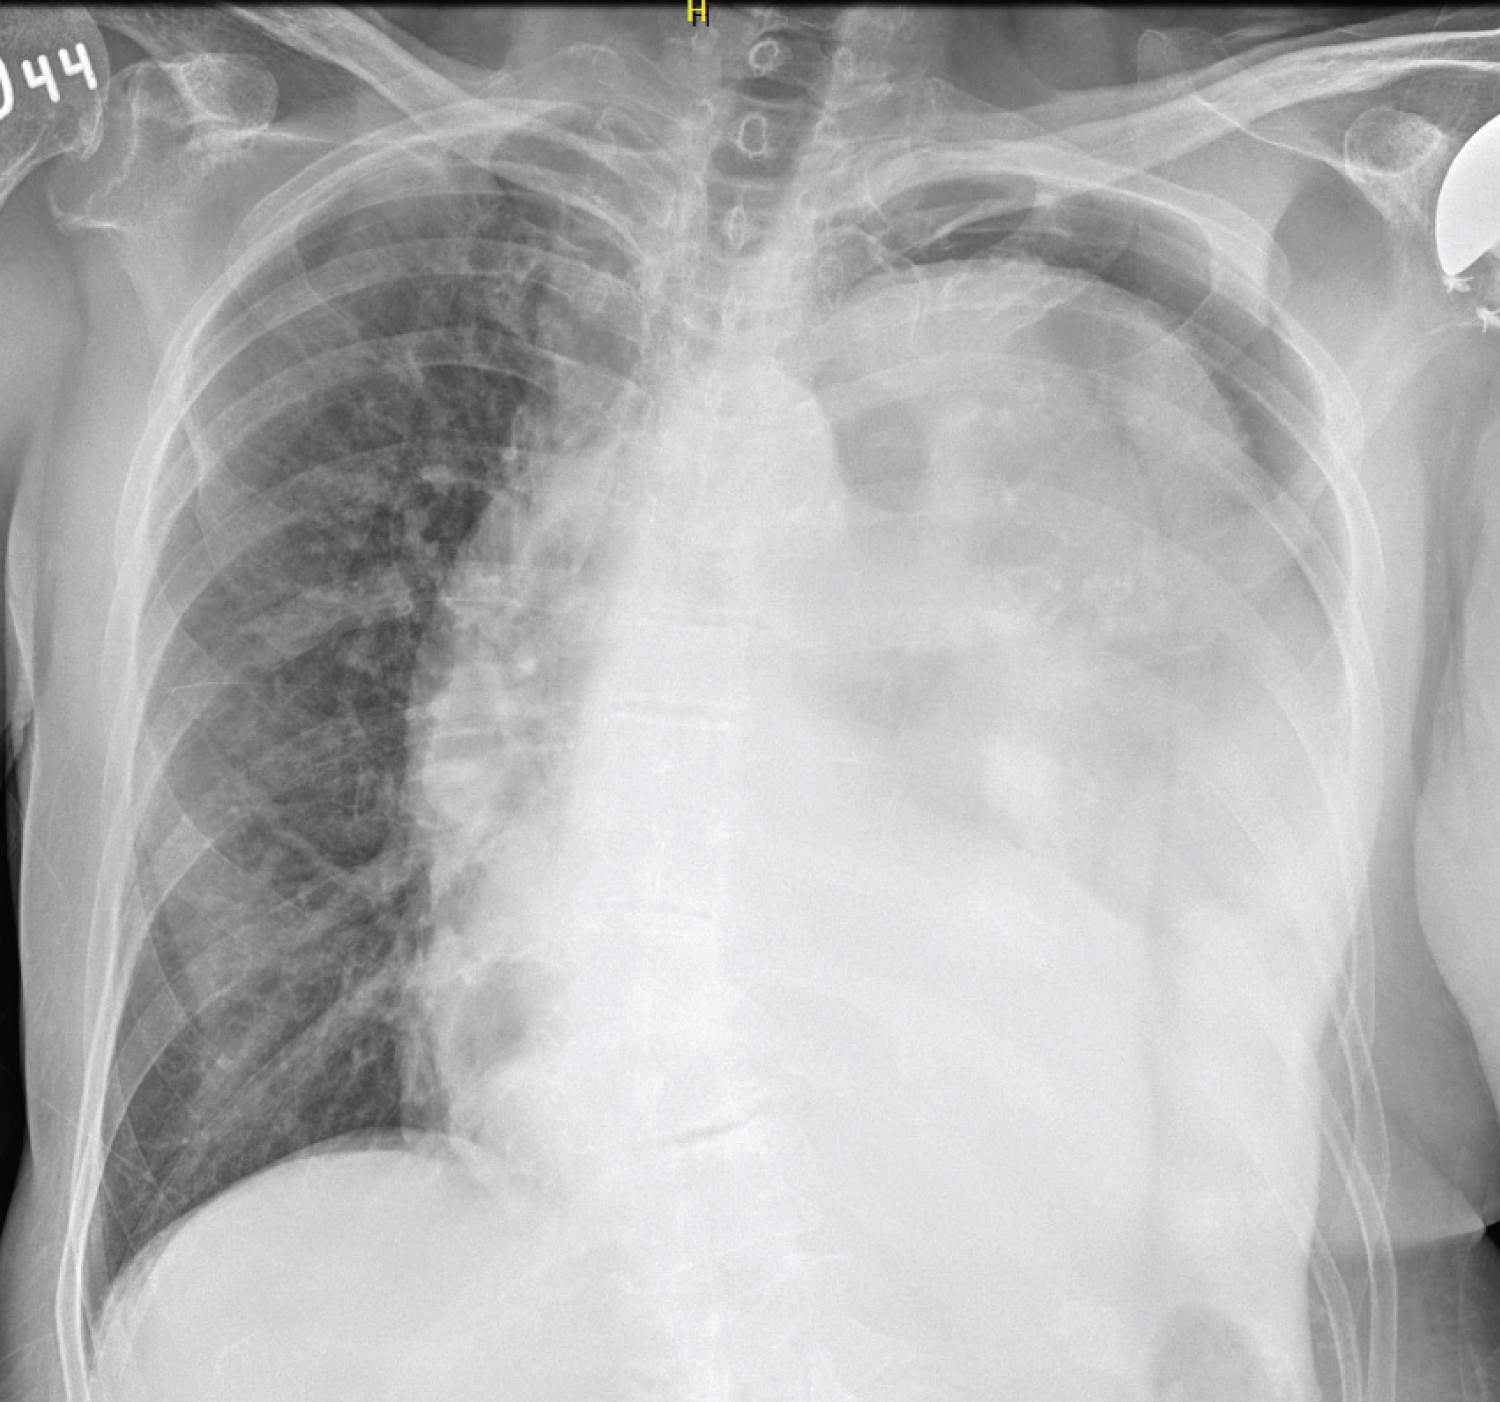

A 79-year-old non-smoking female patient presented with progressive shortness of breath. The patient had a cerebral meningioma 15 years prior, which was managed surgically, with resulting vocal cord paralysis. The patient had been presenting episodes of broncho-aspiration chronically. A year ago, she was presented with an episode of complicated aspirative pneumonia, and had to be taken to surgery. She underwent left thoracoscopic empyema drainage and decortication. At that time no mass was documented. During her follow-up, a rapidly growing mass was found in her left hemithorax, however, during the following 6 months, the mass ceased growth. A trucut biopsy was performed yielding results compatible with an extra-abdominal fibromatous lesion (desmoid tumor). A follow-up chest X-ray revealed a large left pleural mass (Figure 1). Chest CT showed an 18 × 12 × 12 cm mass extending from the lateral chest wall and occupying the entire left hemithorax (Figure 2). After a ten-day pre-surgical nutritional and physical therapy plan, the patient was taken to surgery. A left thoracotomy approach was chosen along with resection of the 6th rib. Despite significant pleural adhesions, the mass itself was not grown into the chest wall. The tumor arose from the left parietal pleura and compressed the inferior left lobe. The mass was in contact with the pericardium, large vessels, and left upper lobe, however it was removed in its entirety without damaging these structures. When the mass was removed (Figure 3), the left lower lobe was found to be eroded and severely affected, requiring a lobectomy. In addition, given the size of the mass, lysis of the left phrenic nerve was performed to allow left hemidiaphragm elevation. The pathology report showed a desmoid tumor with negative margins. In the postoperative period, the patient had a slow recovery secondary to pneumonia and swallowing difficulty. The patient eventually improved and was later discharged.

Figure 1: Chest radiography showing a large mass in the left hemithorax. View Figure 1